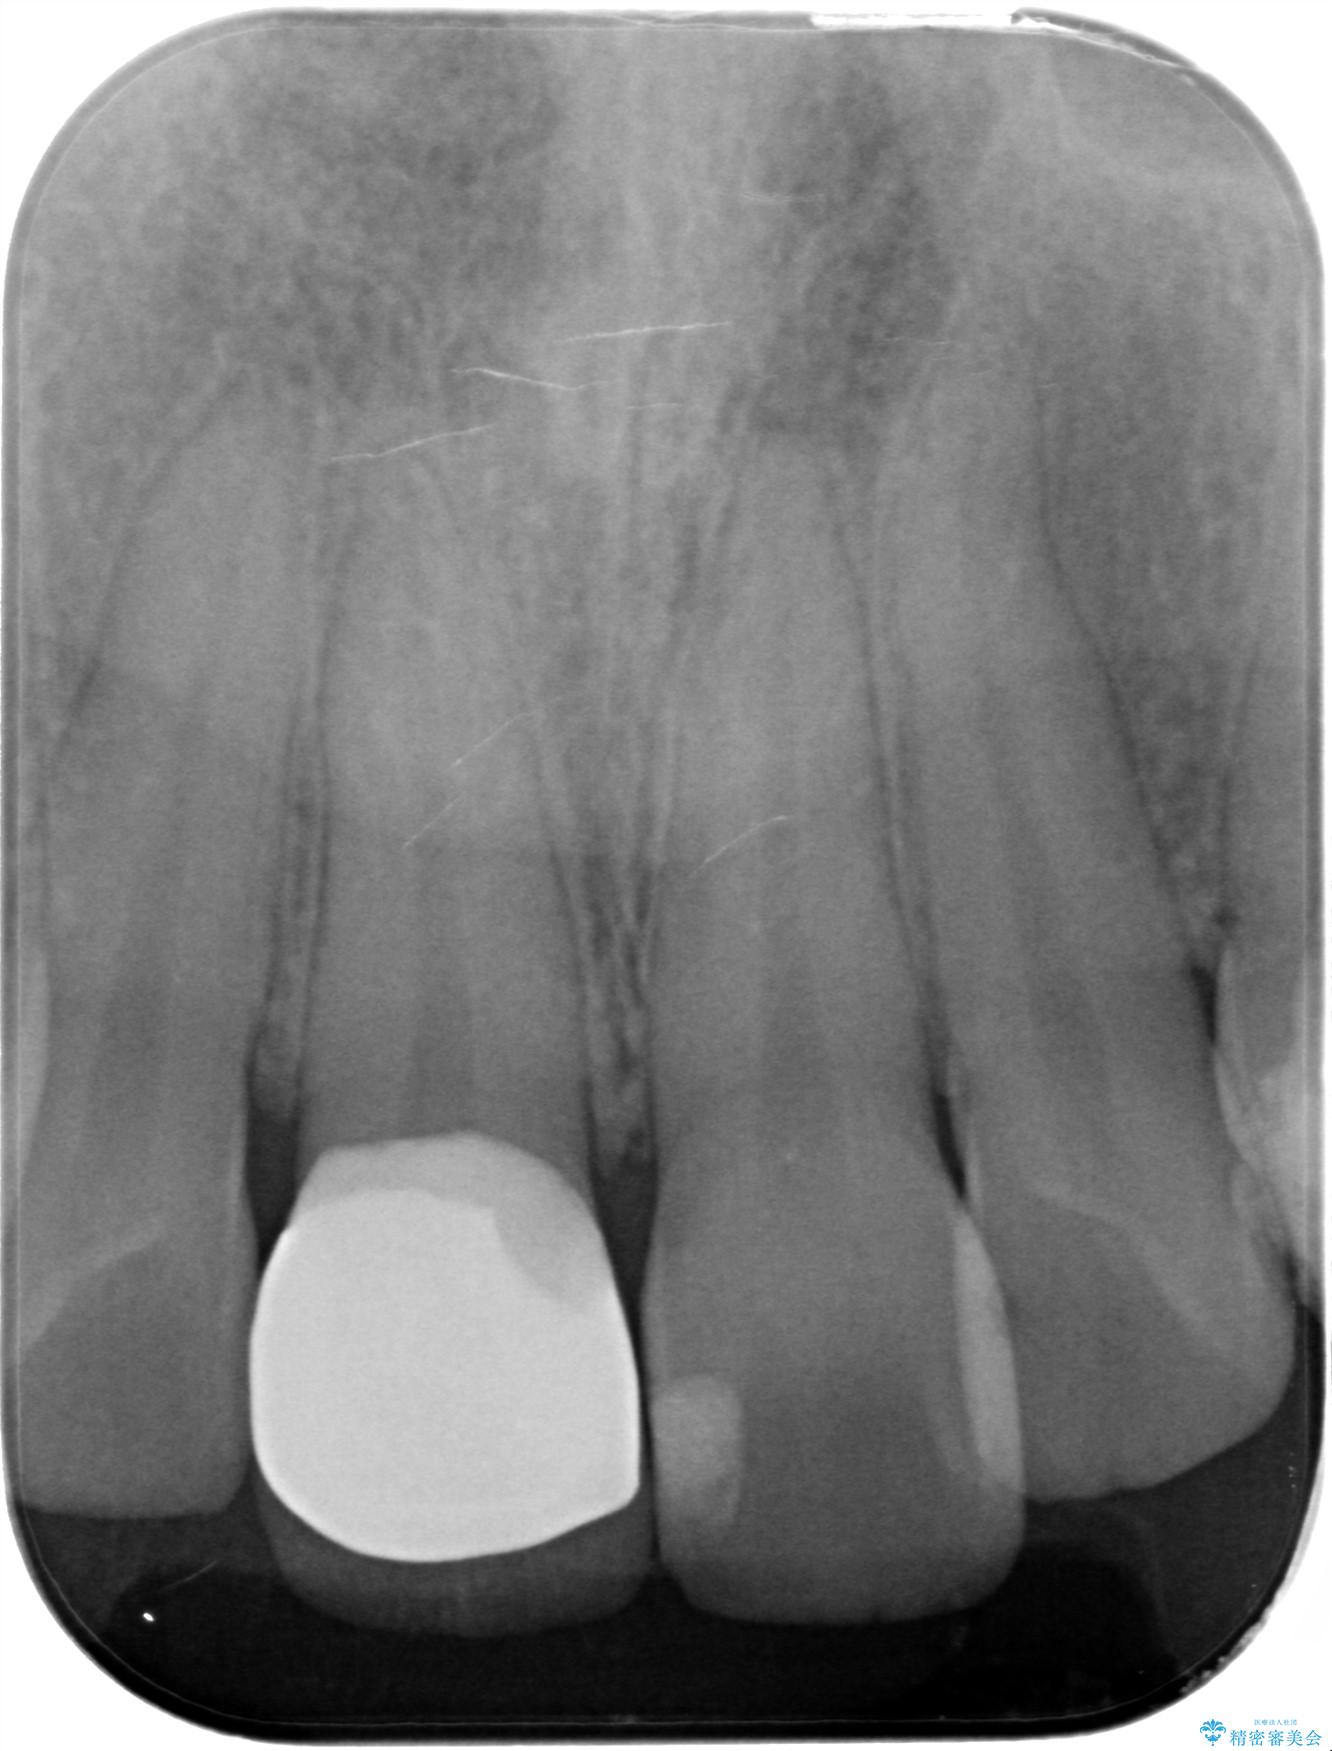

- 前歯のかぶせ物の色が気になるとのことで来院された患者様です。

セラミッククラウンで作り変えていきます。

- 右上1: 仮歯/11,000円、ジルコニアクラウン(スタンダード)/121,000円 合計132,000円(税込)費用は治療当時の料金となります